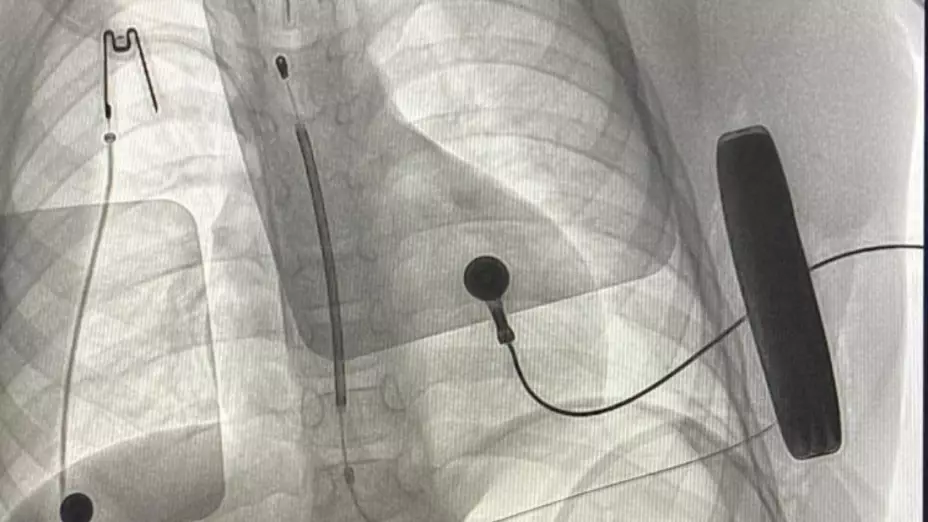

El desfibrilador es un dispositivo subcutáneo, 10 veces más pequeño de los que se utilizan tradicionalmente y protegerá al menor de arritmias cardíacas, provocadas por una cardiomiopatía hipertrófica que engrosa las paredes del corazón.

Por este diagnóstico, al paciente le colocaron el desfibrilador automático implantable, apto para ubicarse bajo la piel delgada de los niños y con el que tendrá protección contra las arritmias.

“Si se presenta una arritmia, este dispositivo la detectará y generará una descarga eléctrica de alto voltaje para restablecer el ritmo cardiaco normal, con lo que evitará la muerte del paciente”, detalló el IMSS.